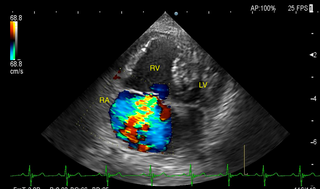

循環器内科 循環器内科 僧帽弁閉鎖不全症、肺高血圧症などを中心に扱います。 リファーラルカテゴリー 猫の腎移植プログラム画像診断科 CT/MRI/超音波検査リハビリテーション整形外科軟部外科神経科(脳脊髄・神経外科)内科鍼治療放射線治療